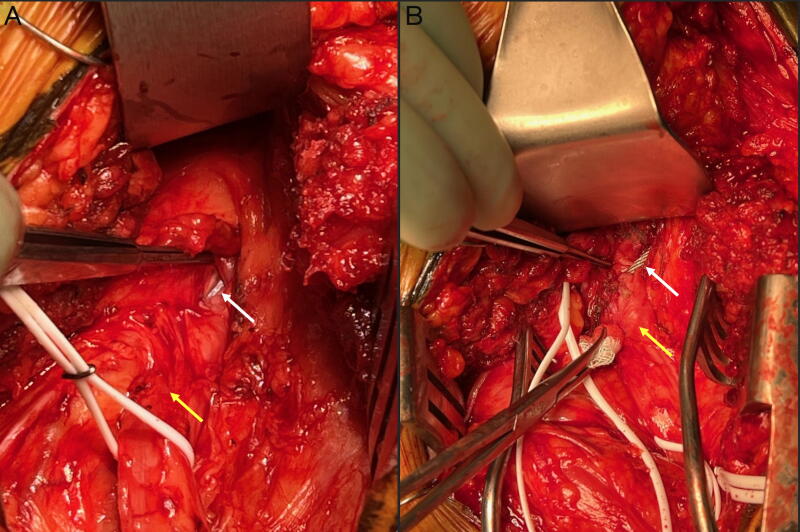

与全髋关节置换术(THA)相关的坐骨神经损伤会导致慢性和进行性残疾。损伤的机制多种多样,管理上的细微差别往往因人而异。我们讨论了一例因先前的全髋关节置换术(THA)造成的股骨环扎钢丝引起的桑德兰4型坐骨神经横断,以强调处理复杂病例时的最佳临床策略。一位 65 岁的女性因同侧髋关节置换术后 1 年开始出现的右坐骨神经感觉运动神经病变恶化、药物难治而来到神经外科门诊就诊。神经系统检查发现她的踝关节背屈/跖屈和足内翻/外翻无力(运动量表 2-3/5)、足趾伸展/屈曲无力(1/5)、足部麻木和过度紧张。肌电图证实了坐骨神经病变。磁共振神经图(MRN)显示,右侧坐骨神经增粗,与股骨环扎线相连,在重建的计算机断层扫描成像中显示为连续的。术中发现,该钢丝明显横断并留在坐骨神经内,需要骨科会诊并在横断处剪断钢丝。切除了周围的神经瘤,并使用神经异体移植插管重建了缺损。术中神经电生理监测(IONM)信号保持稳定。X光片证实钢丝断开过程并不复杂。患者第二天就出院回家了,随访1个月后症状明显缓解。股骨卡环钢丝导致坐骨神经横断并持续神经压迫的延迟病例非常罕见。损伤的解剖结构可能是高风险的,这就要求在 THA 和神经成形术病例中制定周密的手术计划。策略包括术前 MRN 评估神经损伤的病理解剖、神经外科和矫形外科联合管理以及多模式 IONM,以降低术中神经损伤的风险并优化预后。

Sciatic nerve injury associated with total hip arthroplasty (THA) confers chronic and progressive disability. Mechanisms of injury are heterogeneous and management nuances are often case-specific. We discuss a Sunderland Type 4 sciatic nerve transection by femoral cerclage wire from prior THA to highlight optimal clinical strategies when approaching complex cases. A 65-year-old woman presented to the neurosurgery clinic with worsening, medically refractory right sciatic sensorimotor neuropathy that began 1 year after ipsilateral hip arthroplasty. Neurological examination detected weakness in ankle dorsiflexion/plantarflexion and foot inversion/eversion (motor scale 2-3/5), toe extension/flexion (1/5), foot numbness, and hyperesthesia. Electromyogram confirmed sciatic neuropathy. Magnetic resonance neurogram (MRN) showed a thickened right sciatic nerve abutting a femoral cerclage wire, which appeared contiguous on reconstructed computed tomography imaging. Intraoperatively, the wire was discovered to have clearly transected and remained lodged within the sciatic nerve, requiring orthopedic surgery consultation and wire cutdown at the transection site. The surrounding neuroma was excised and the defect was reconstructed using nerve allograft interposition. Intraoperative neurophysiology monitoring (IONM) signals remained stable. Radiographs confirmed uncomplicated wire disconnection. The patient was discharged home the next day and reported significant symptomatic relief at 1-month follow-up. Delayed presentation of sciatic nerve transection by femoral cerclage wire with ongoing neural compression is rare. The anatomy of injury can be high risk, impelling thoughtful operative planning in THA as well as neuroplasty cases. Strategies include preoperative MRN to evaluate the pathoanatomy of nerve injury, neurosurgery and orthopedic surgery comanagement, and multimodal IONM to reduce risks of intraoperative neural injury and optimize outcomes.